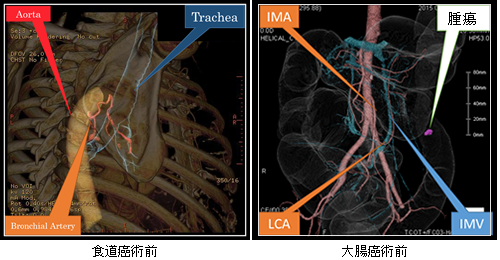

●3D‐CTなどの最新機器を駆使して術前シミュレーションを実施して、安全で確実な手術をめざします。

きずが小さい手術(低侵襲手術:胸腔鏡・腹腔鏡手術[ロボット支援下手術を含む])を積極的に実施しています。進行がんに対しても安全性が確保できると判断した症例では実施しています。きずが小さいと美容面で有利なだけでなく、早期の回復が期待できます。

より安全性が高い術式を採用しています。国内のガイドラインで疾患ごとに標準とされる手術方法はある程度決まっていますが、吻合方法(食道や胃などの消化管をつなぎ合わせる方法)などは施設や術者の裁量に任されています。当チームではこれまでの臨床経験や学術論文などの客観的な指標をもとに検討し、個々の症例に対してより安全性が高いと思われる術式を選択しています。